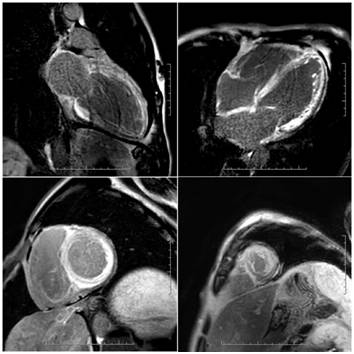

心脏MRI

心脏MRI特点

心脏淀粉样变中晚期钆强化(LGE ,late gadoliniumenhancement )极为常见,由淀粉样蛋白沉积引起的间质膨胀产生。在诊断心脏淀粉样变中具有极高的特异性。

弥漫性透壁或心内膜下LGE最为常见。相当一部分患者在LV出现形态学增厚前已存在异常LGE,因此心脏MRI具有早期检出心脏浸润的潜力。

这两个特征均可出现在心室肌和心房。